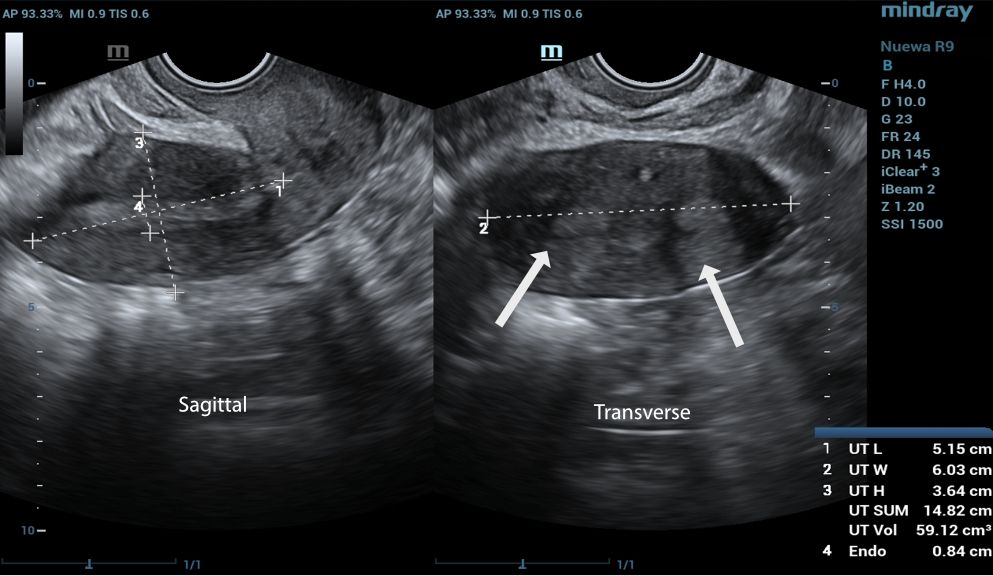

A transvaginal two-dimensional (2D) gynecologic ultrasound was initially performed, capturing both transverse and sagittal views of the uterus.

two endocervical cavities noted

There are two endocervical cavities noted

During the ultrasound examination, we observed a normal vagina and two cervixes. On the transverse view, two distinct endometrial echoes were visualized, raising suspicion for a possible congenital uterine anomaly such as a septate or bicornuate uterus.

To further assess the anatomy, a 3D ultrasound was conducted, which provided the true coronal view of the uterus. This enabled better visualization of the uterine cavity and external contour, allowing for more accurate classification.

Based on the 3D ultrasound findings, the impression was complete septate uterus with septate cervix.